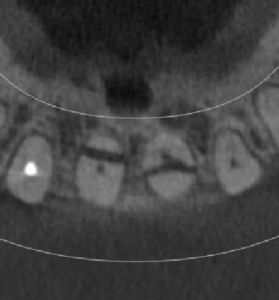

앞니부분에 치근이 파절된 모습이 보이는 CT 횡단면